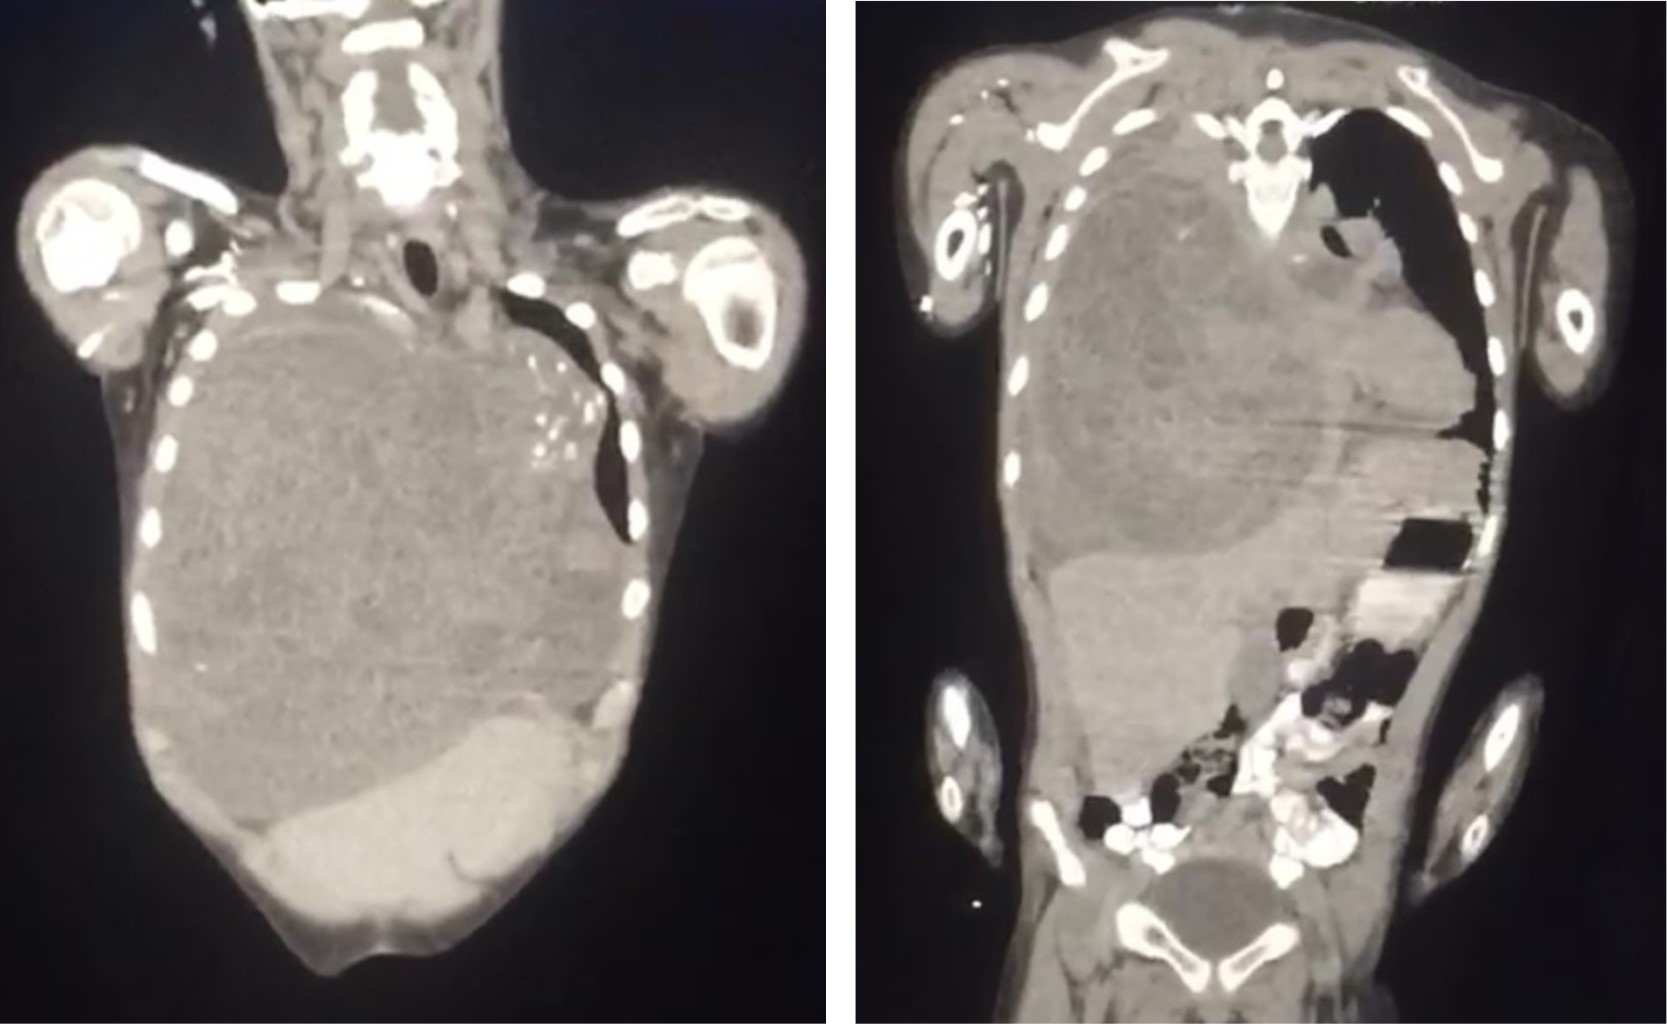

Se inicia esquema de tratamiento basado en tres ciclos de quimioterapia neoadyuvante estándar con bleomicina, etopósido y cisplatino. Los marcadores tumorales después de la quimioterapia mejoraron notablemente durante los primeros dos ciclos; sin embargo, el control radiográfico mostró un crecimiento tumoral que ocupa 80% del hemitórax derecho con aumento en el desplazamiento de las estructuras mediastinales (Figura 2). Se optó por continuar el tercer ciclo de quimioterapia, los marcadores tumorales permanecieron sin cambios, se decide realizar tomografía toracoabdominal como estudio de extensión para descartar metástasis. Lamentablemente, se evidencia un crecimiento exponencial del tumor que ocupaba 100% del hemitórax derecho y mediastino anterior sobrepasando más allá de la línea media del cuerpo con colapso del pulmón derecho, desplazamiento del corazón y grandes vasos hacia el lado izquierdo así como los componentes del mediastino posterior como tráquea y esófago, el abdomen sin evidencia de metástasis (Figura 3). Se realizó ecocardiograma transtorácico con datos de disfunción diastólica del ventrículo derecho con compresión de la aurícula derecha y vena cava inferior, hipertensión arterial pulmonar moderada, levocardia, levoapex, desplazamiento extremo del corazón a la línea axilar media, lo que implicaba empeoramiento clínico de nuestro paciente.

Los hallazgos quirúrgicos fueron: un tamaño tumoral de 30 × 23 × 15 cm ubicado en mediastino anterior, forma ovoide, superficie lisa y blanda, peso de 5 kg (Figura 4), que ocupa casi todo el hemitórax derecho con colapso pulmonar completo, la región superior del hemitórax izquierdo con desplazamiento extremo del corazón y grandes vasos, con compresión casi total de vena cava superior.